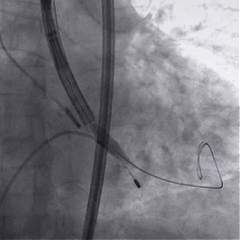

术中影像

根部造影

球囊预扩

瓣膜稳定释放

瓣膜展开后造影

再次造影,确认瓣膜位置

稳定脱钩

最终造影,瓣膜位置良好,无明显瓣周漏

外周血管检查